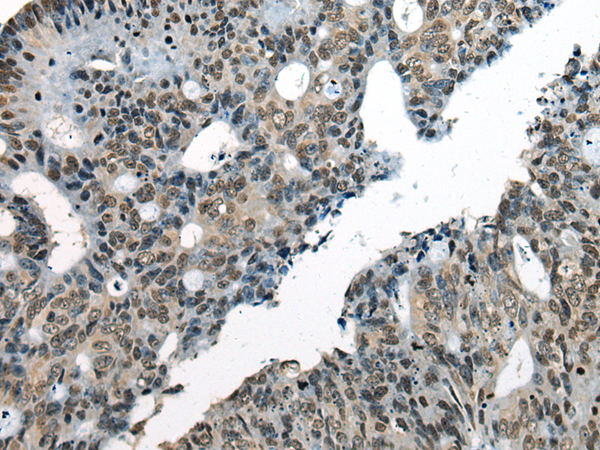

This gene encodes a DNA helicase protein involved in DNA repair. The protein converts ATP to add poly(ADP-ribose) as it regulates chromatin relaxation following DNA damage. Several alternatively spliced transcripts variants have been described for this gene. |

ELISA, IHC |

CHD1L |

chromodomain helicase DNA binding protein 1 like |

IHC positive control: |

Human colorectal cancer |

IHC Recommend dilution: |

25-100 |